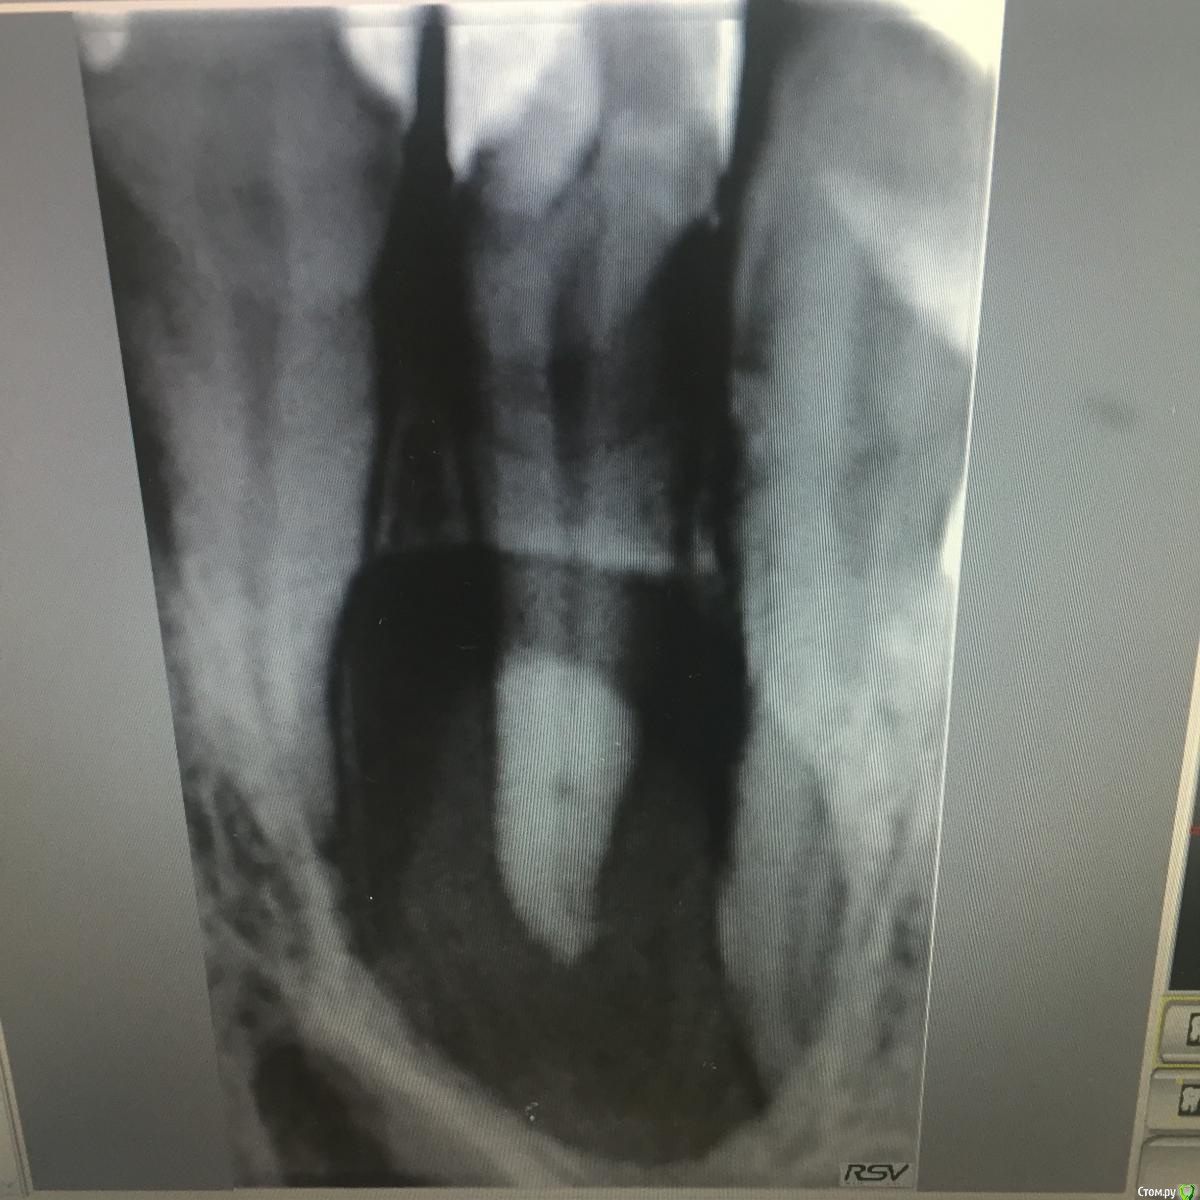

Ирина Игоревна Опубликовано 26 сентября, 2017 Поделиться Опубликовано 26 сентября, 2017 Обратилась пациентка. 1.2 зуб не беспокоит, ранее восстановлен композитным виниром. Отечность со стороны нёба. Хотела бы посоветоваться, правильно ли мной выбрана тактика лечения. Решила проводить по стандартному протоколу периодонтита: кофер, обработка профайлами, эдта, хлорка, 2% хлоргексидин. Отделяемого из канала не получила. В канал- кальций. Времянка. Разрез по нёбу. Получен отток. Сомневаюсь потому что очаг воспаления очень большой, хотя знаю что размера пугаться не стоит, думала что из канала польётся - не полилось( и отечность со стороны нёба не характерна обычно,чаще по переходной. Правильно ли мной поставлен диагноз и разработан план лечения? Ссылка на комментарий

Л Ю С Я Опубликовано 26 сентября, 2017 Поделиться Опубликовано 26 сентября, 2017 Это же боковой резец. У них апекс чаще отклонён небно. Вот и вырос очаг в ту сторону. Ведите по периодонтиту 2 Ссылка на комментарий